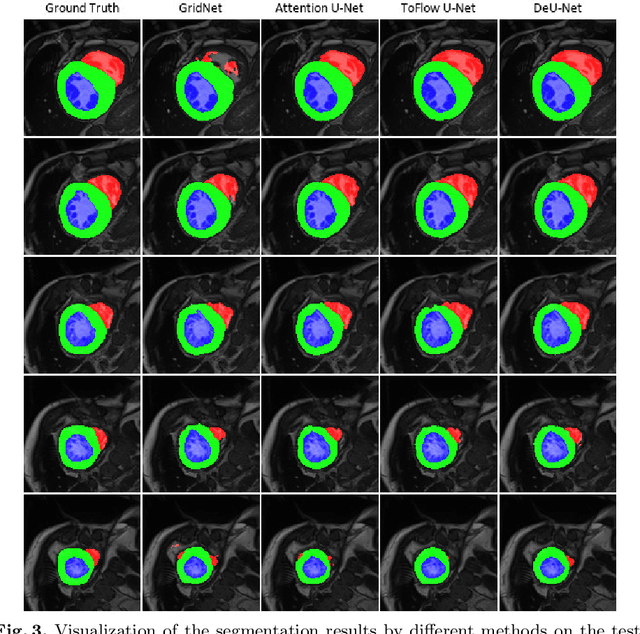

Abstract:Automatic segmentation of cardiac magnetic resonance imaging (MRI) facilitates efficient and accurate volume measurement in clinical applications. However, due to anisotropic resolution and ambiguous border (e.g., right ventricular endocardium), existing methods suffer from the degradation of accuracy and robustness in 3D cardiac MRI video segmentation. In this paper, we propose a novel Deformable U-Net (DeU-Net) to fully exploit spatio-temporal information from 3D cardiac MRI video, including a Temporal Deformable Aggregation Module (TDAM) and a Deformable Global Position Attention (DGPA) network. First, the TDAM takes a cardiac MRI video clip as input with temporal information extracted by an offset prediction network. Then we fuse extracted temporal information via a temporal aggregation deformable convolution to produce fused feature maps. Furthermore, to aggregate meaningful features, we devise the DGPA network by employing deformable attention U-Net, which can encode a wider range of multi-dimensional contextual information into global and local features. Experimental results show that our DeU-Net achieves the state-of-the-art performance on commonly used evaluation metrics, especially for cardiac marginal information (ASSD and HD).